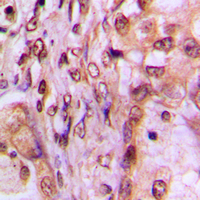

IHC (Immunohiostchemistry)

(Immunohistochemical analysis of MAF1 staining in human breast cancer formalin fixed paraffin embedded tissue section. The section was then incubated with the antibody at room temperature and detected using an HRP conjugated compact polymer system. DAB was used as the chromogen. The section was then counterstained with haematoxylin and mounted with DPX.)